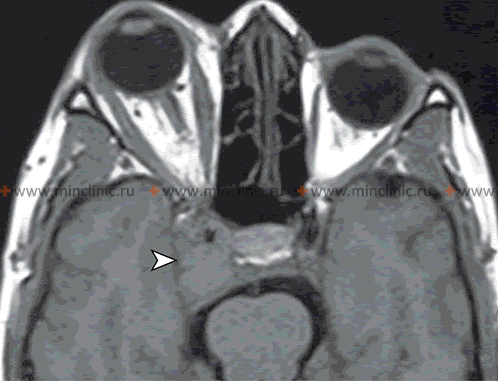

Neuroimaging techniques like Magnetic Resonance Imaging (MRI) play a crucial role in evaluating suspected orbital and potential intracranial complications arising from inflammation of the nasal cavity and paranasal sinuses.

- MRI of the Orbits and Brain with Gadolinium Contrast: MRI provides superior soft tissue contrast and is often complementary or preferred if CT is equivocal, if intracranial complications are strongly suspected, or for evaluating specific structures like the optic nerve or cavernous sinus [9]. Advantages include:

- Better differentiation between phlegmon (diffuse inflammation/cellulitis) and drainable abscess.

- Superior visualization of optic nerve inflammation (optic neuritis).

- High sensitivity for detecting early intracranial complications like meningitis (leptomeningeal enhancement), epidural/subdural empyema, brain abscess.

- Excellent evaluation of cavernous sinus pathology (thrombosis, inflammation) - often combined with MR Venography (MRV).

- Diffusion-weighted imaging (DWI) sequence is highly sensitive for detecting restricted diffusion within abscess collections (pus), confirming their purulent nature.